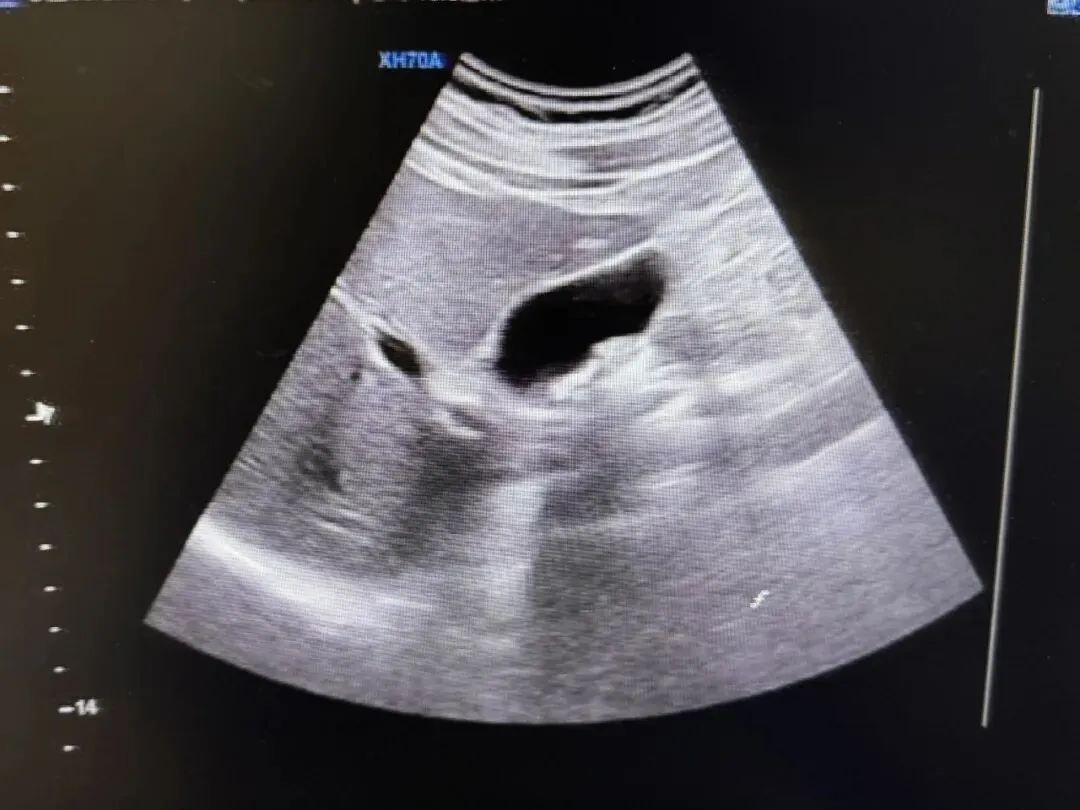

超声表现

● 慢性胆囊炎病程初期,胆囊体积无明显变化或可增大,超声成像难以发现和识别。病程时间较长,反复发作后可见胆囊缩小变形,甚至呈实质性团块状强回声。

● 胆囊壁增厚,毛糙,回声增强。

● 胆囊内透声差。

● 脂餐试验显示胆囊收缩功能差或无功能。

胆囊结石并慢性胆囊炎。